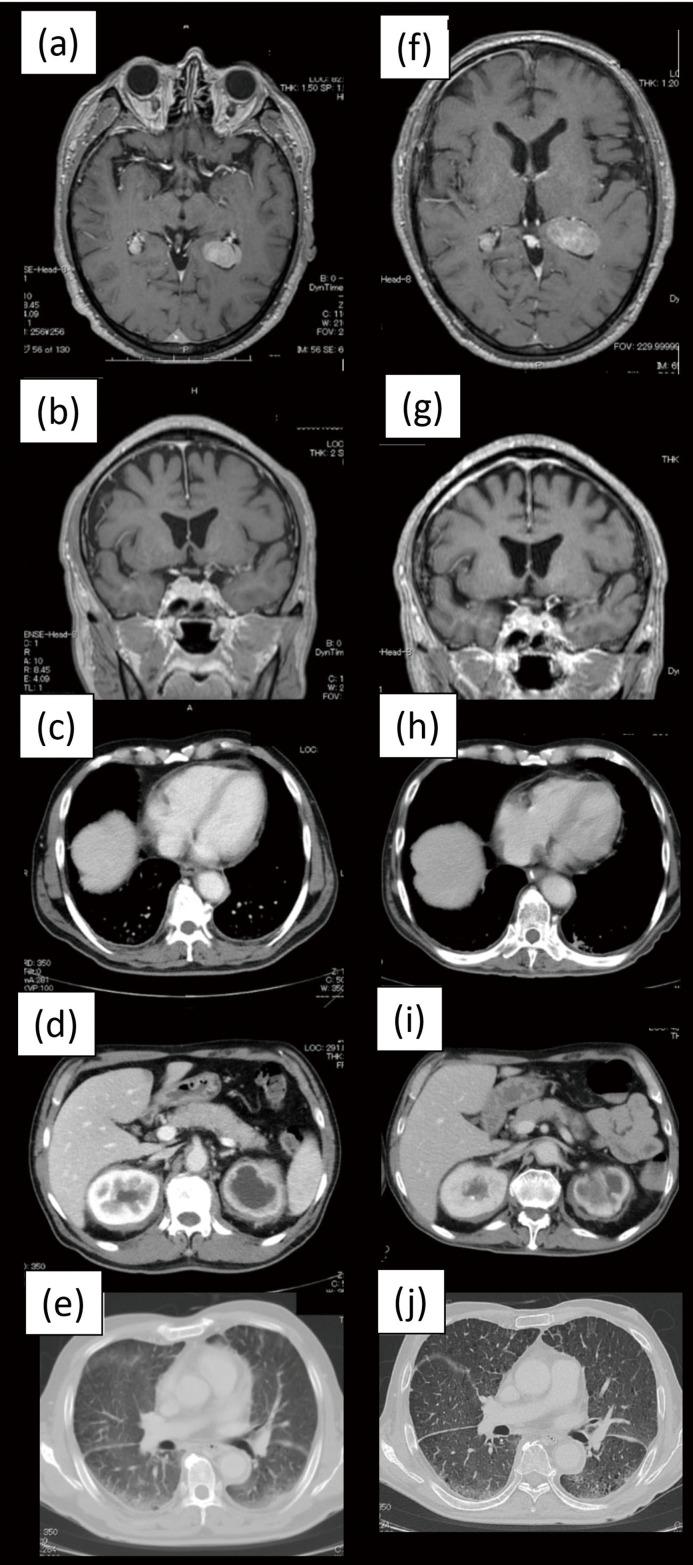

Erdheim-Chester disease (ECD), a rare form of non-Langerhans cell histiocytosis, is characterized by the infiltration of foamy CD68 and CD1a histiocytes into multiple organ systems. Central nervous system (CNS) involvement has recently been reported to be a poor prognostic factor when treating ECD with interferon alpha. We report the case of a 66-year-old Japanese patient with ECD involving the CNS who harbored the BRAF V600E mutation and also concomitantly developed polycythemia vera with the JAK2 V617F mutation. We confirmed 2-chlorodeoxyadenosine (cladribine) therapy to be effective for the patient in this case.

厄德里希-切斯特病(ECD)是一种罕见的非朗格汉斯细胞组织细胞增多症,其特征是泡沫状CD68和CD1a组织细胞浸润多个器官系统。最近有报道称,在使用干扰素α治疗ECD时,中枢神经系统(CNS)受累是一个不良预后因素。我们报告了一例66岁的日本ECD患者,其CNS受累,携带BRAF V600E突变,同时还并发了伴有JAK2 V617F突变的真性红细胞增多症。我们证实,在该病例中,2-氯脱氧腺苷(克拉屈滨)治疗对该患者有效。